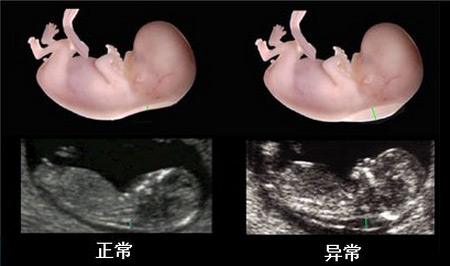

NT即nuchal translucency的缩写,它指的是“颈项透明层”,也就是胎儿颈椎水平矢关切面皮肤至皮下软组织之间的最大厚度。NT检查也是早期唐氏筛查的诊断依据之一,检查目的是为了在妊娠较早阶段诊断染色体疾病和发现多种原因造成的胎儿异常。通过彩色超声检查胎儿的颈椎厚度,是排除胎儿畸形的一种常规检查!如果检查结果超过3mm,常提示有不良胎儿结局。需要重点记录,便于在后期的唐氏筛查(16-18周)和四维彩超(24周)排挤检查时提示医生重点关注。

NT筛查是通过B超测胎儿颈部透明带厚度。颈部透明带是指胎儿颈部后方皮下积水的空隙,进行超音波扫描时,医师会详细测量介于皮肤和组织之间的空隙厚度,染色体异常的胎儿,其颈部透明带会明显增厚,特别是唐氏症儿。通常唐氏症较易发生在高龄产妇身上,医学文献已证实当胎儿后颈部透明带越厚,染色体异常的机率就越高。